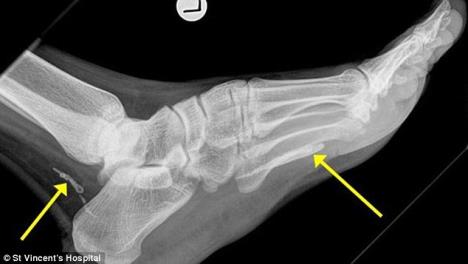

Rendgenski snimak stopala muškarca (38), australijskog imigranta iz Sudana, otkrila je da mu je u peti živeo gvinejski crv, parazit koji izjeda telo iznutra.

Doktori su zaključili da je parazit u stopalu živeo oko četiri godine, a narastao je do skoro metar dužine... Uklonjen je operacijom i pacijent se oporavlja.